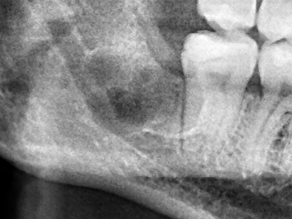

為了健保患者拔智齒的安全,遠離唇麻、舌麻、口鼻竇炎、大出血...等併發症,

☆本院特別巨資增設 ”千萬級3D AI透視電腦斷層”,並配合“成骨膠原蛋白”施作 (上述兩項目前健保無給付),讓您遠離神經傷害、口鼻竇(炎)相通...等併發症,除健保之外,難免會有避免併發症風險的自費項目,網路上經常會有看到智齒拔完後唇麻、舌麻、口鼻竇相通等併發症,在本院嚴格自我要求下,此類併發症在本院幾乎趨近於零。

(兩條紅線中間黑色區域即為神經管)

外面拔完時常術後唇麻舌麻,本院發生趨近於零